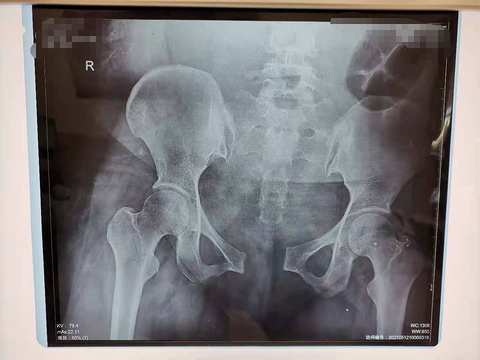

产后三天发现耻骨联合分离达4.8厘米,无法下地行走

看到一位医生分享的,一位准妈妈,产后三天发现耻骨联合分离达4.8厘米,无法下地行走,卧床休息时腿都得屈着,太痛苦!后经会诊给予正骨复位治疗四天后,耻骨联合分离恢复到1.7厘米,很有成就感啊!

顺产后12天,耻骨联合分离导致疼痛,一检查发现分离了4.5CM

知道生孩子会导致耻骨分离,但是这个妈妈分离4.5厘米有点吓人哦,4.5厘米大概有————————差不多这么宽吧?据说勒个妈妈孩子出生体重4050克,产后当天就不能翻身、下床。产后一周才能在家属搀扶下站立,但却无法正常行走,只能侧身挪步前行。 所以说孕期体重控制还是很重要,娃儿太大了,最后受罪的还是大人。